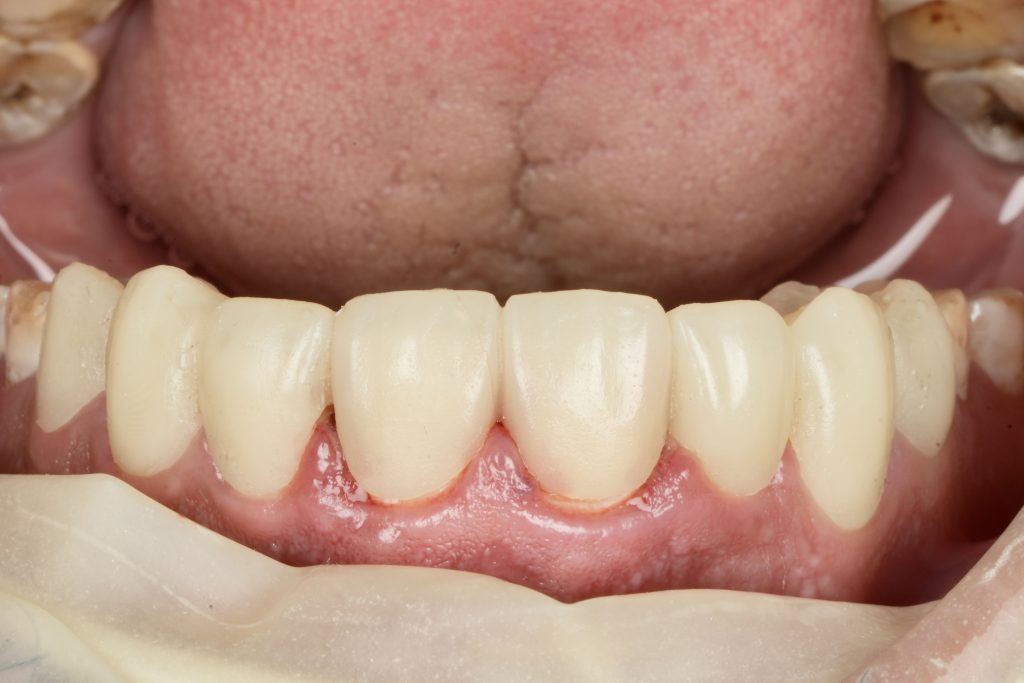

IPS E-max Press veneers were pressed and characterized using micro-layered incisal ceramics for vitality and translucency. Surface texture and internal effects were customized to simulate natural perikymata and halo zones (Fig 3).

Margins were refined using fine diamond strips, and surface gloss was enhanced with a multi-step polishing system (Shofu OneGloss + OptraPol Next Gen). Post-operative evaluation showed ideal incisal translucency, line-angle symmetry, and gingival health (Fig 5 & 6).